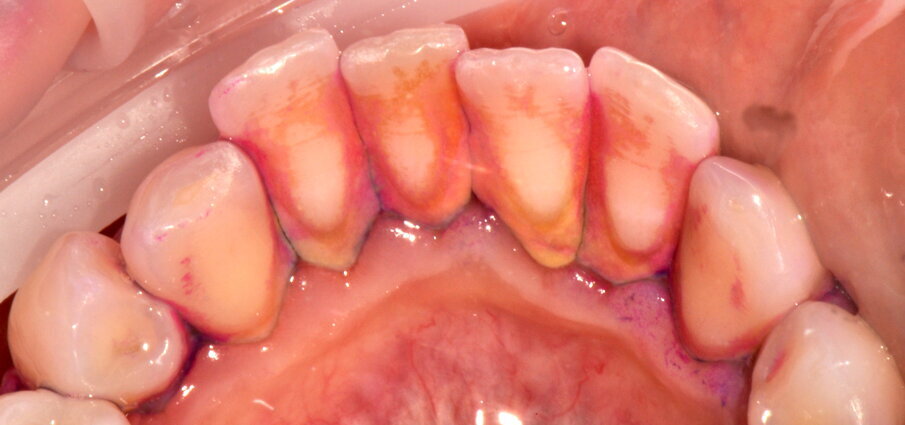

- Rimozione della placca dai tessuti orali (gengiva, mucosa orale, lingua e palato) con polveri a bassa abrasività (polvere di Eritritolo - Polvere PLUS® EMS) rimuovendo completamente il reservoir batterico dai tessuti, si effettua usando il manipolo sopra-gengivale con livello di potenza 30%, di irrigazione 70% e distanza 5-10 mm ( 2a-2c);

Figg. 2a-2c - Foto scattate dopo l’utilizzo del manipolo sopra-gengivale, nelle aree vestibolare (2a), palatale (2b) e linguale (2c), senza la detartrasi con strumento piezoelettrico.